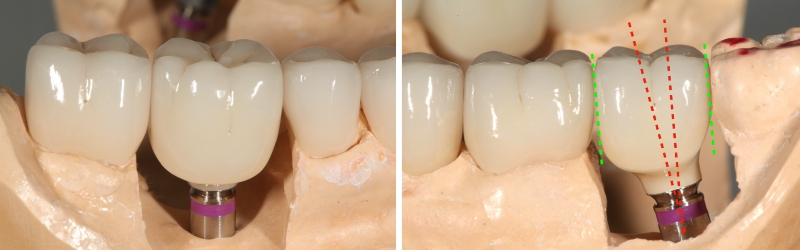

The negative consequence of altering the implant restoration form interproximally to allow this surface to pass by the adjacent tooth is the opening of the interdental gingival embrasure, which may result in a lateral food impaction area.

If a restoration insertion path problem cannot be solved by altering an interproximal surface, a cemented restoration may be required. If a two-piece abutment and crown are fabricated, I want you to know that what goes into the implant dictates the insertion path in addition to the interproximal contacts of the adjacent teeth.

Suppose you fabricate a separate abutment and crown to cement them together to make a one-piece screw-retained restoration. In that case, you should be careful if you try them independently. The abutment’s crown insertion path may differ from the abutment’s insertion path into the implant.